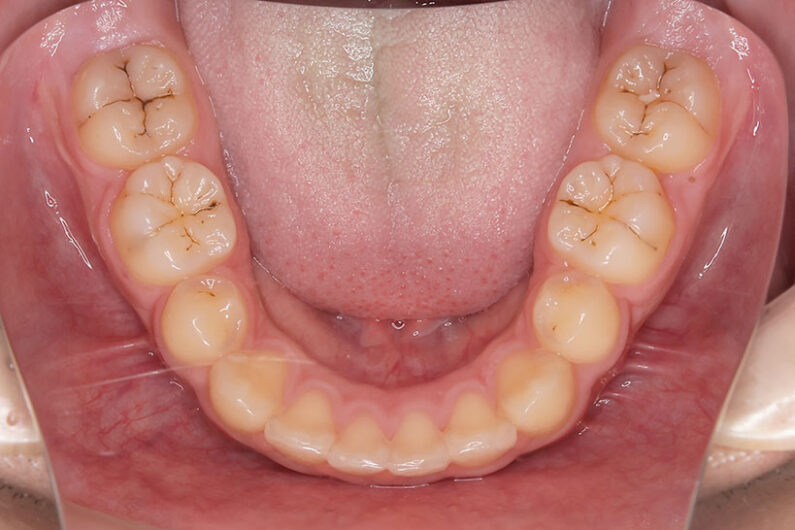

右上の前歯が生えてこない事を気にされ来院されました。 レントゲン写真から、上顎正中に過剰歯が埋伏していることが原因でしたので、抜歯して経過観察。 遅れて、無事に生えてきました。 もし、自然に生えてこない場合は、開窓して、引っぱり出します。(廷出) 状態により、引っぱり出せない場合もあります。 将来的にスペース不足により、上下顎前臼歯部に重度の叢生(がたつき)が予測できますので、がたつきを減らすために、小児矯正で側方拡大を行いました。 小児矯正で側方拡大を行ってもスペースが足りない場合(著しくスペース不足の場合)は、がたつき(叢生、八重歯)が残ります。 残ったがたつき(叢生)は、本格矯正ですべて生え変わった中学生から治せば問題ありません。 来院間隔が平均で1.5カ月でしたので半年ほど治療期間が長いです。